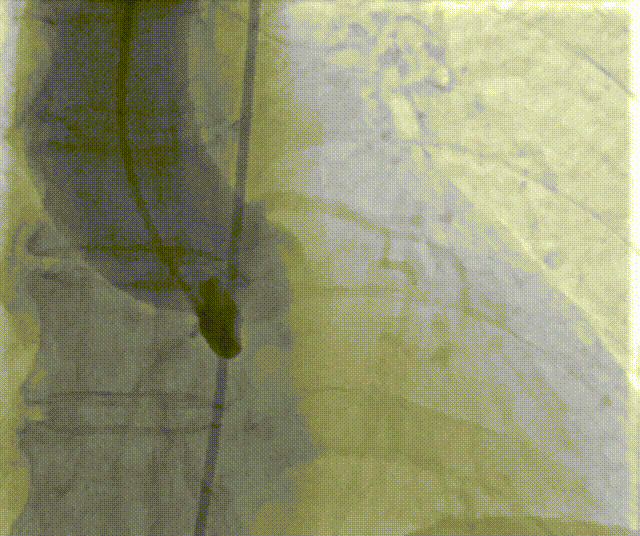

手术过程